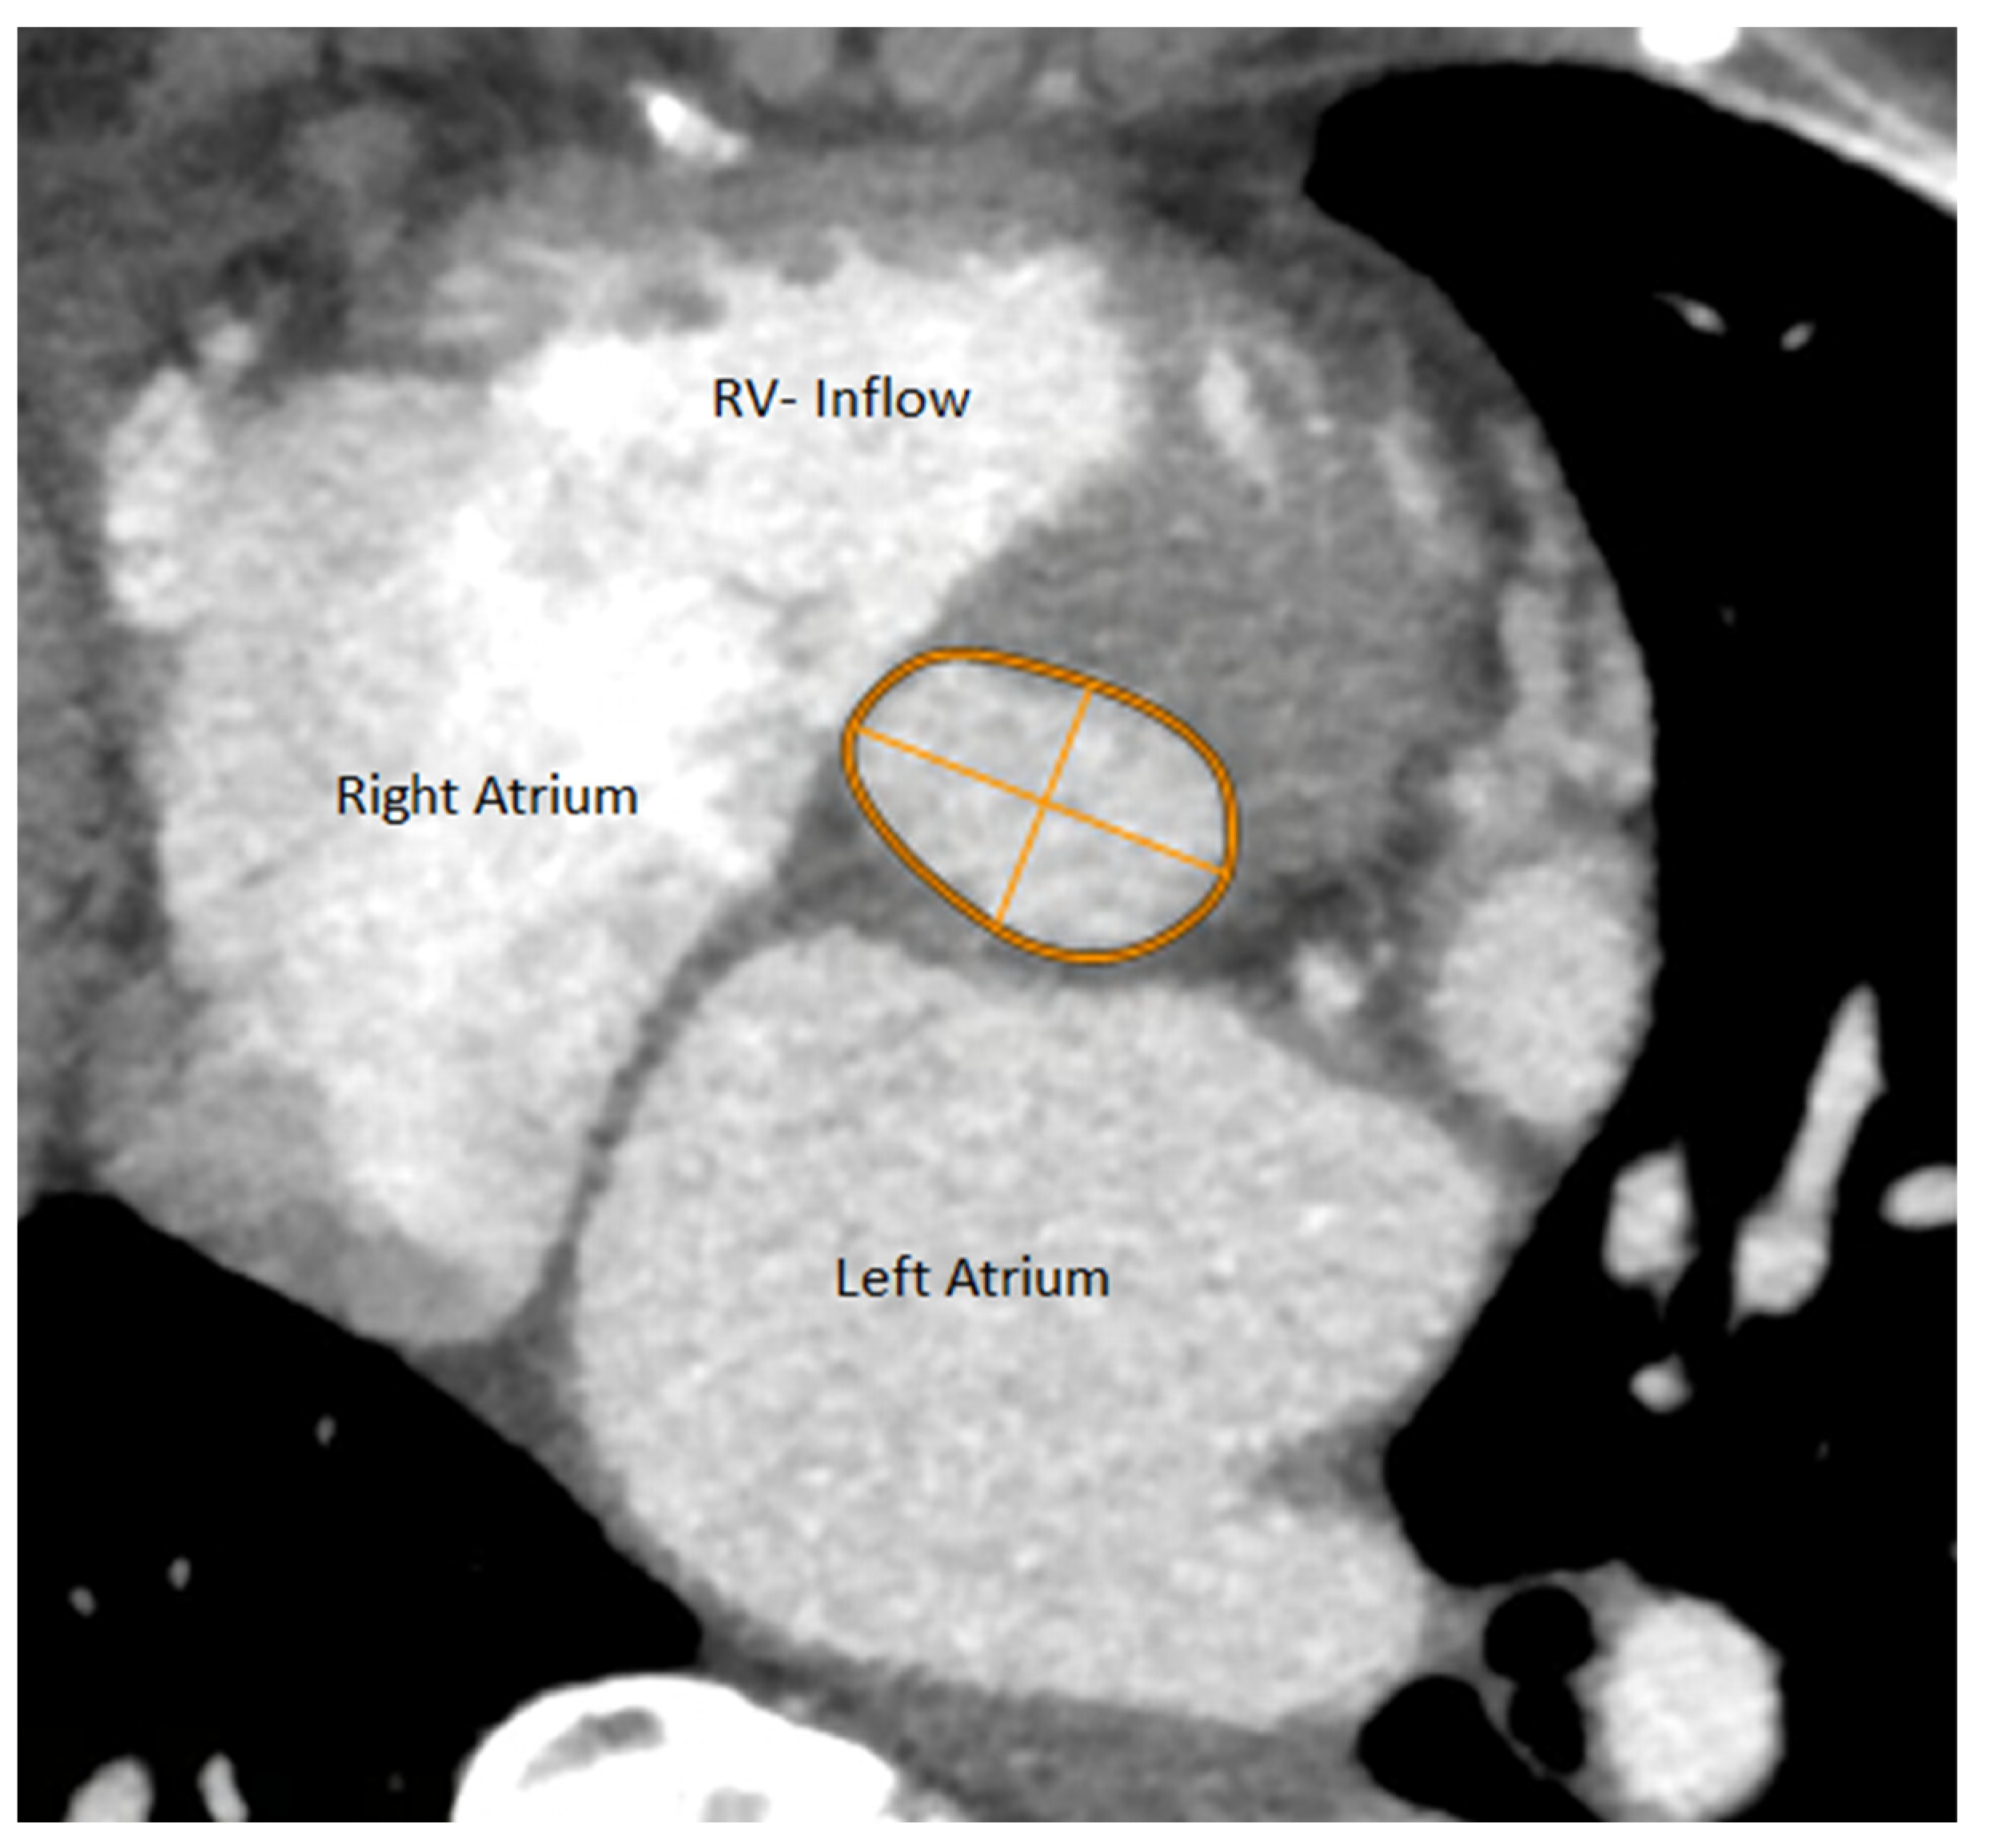

Aortic annulus was defined as the level at which nadir points of the three aortic cusps could be seen in one plane. The Phillips portal was used to find the plane, which was thereafter checked and corrected manually as needed. Aortic annulus appears nearly elliptic in the annular plane. Following the reconstruction of the aortic valve annulus in the annular plane, the long and short axes of this ellipse were measured. Also, the perimeter and area of the aortic annulus were measured within the same plane (Figure 1 and Figure 2).

Figure 1.

Slice through the heart within the Aortic Annulus plane with parameters measured upon MDCT.